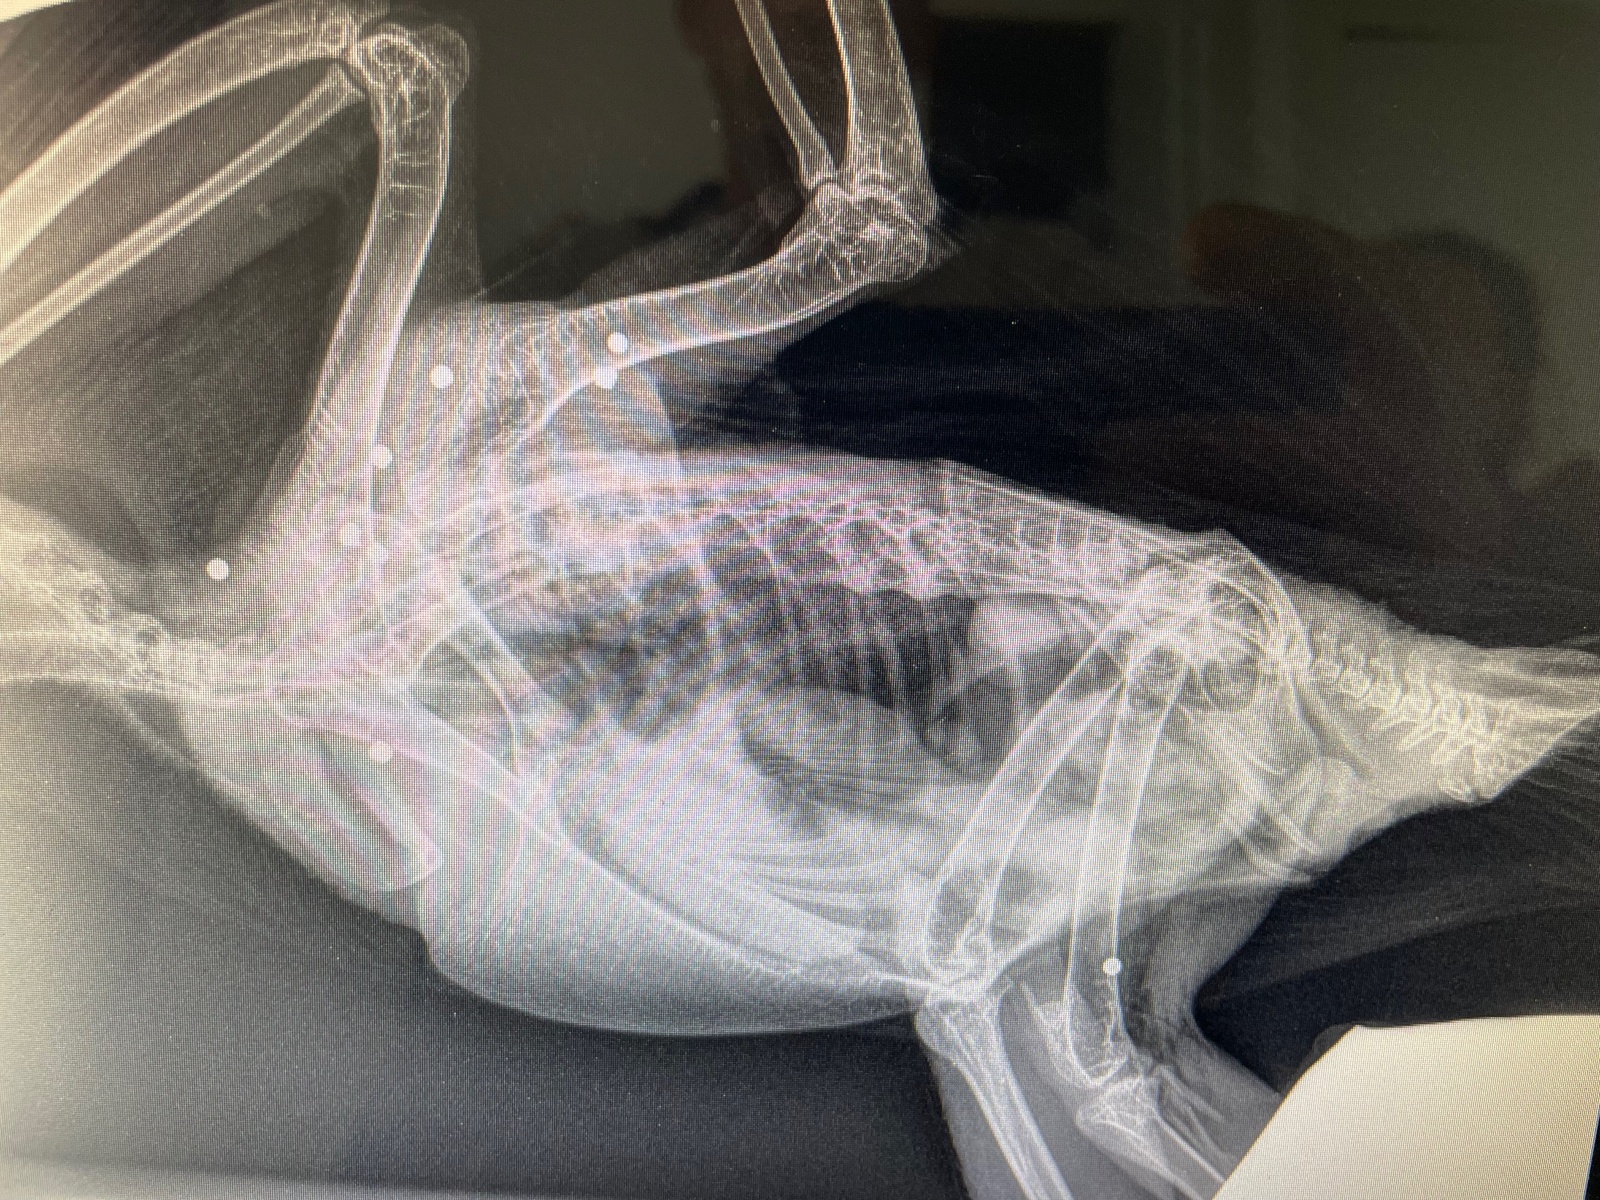

Fin avril, un Faucon pèlerin a été la cible de tirs au plomb. L'oiseau a été déposé à la Réserve Africaine de Sigean pour des soins, puis transféré à un centre de soins par la LPO.

Photos